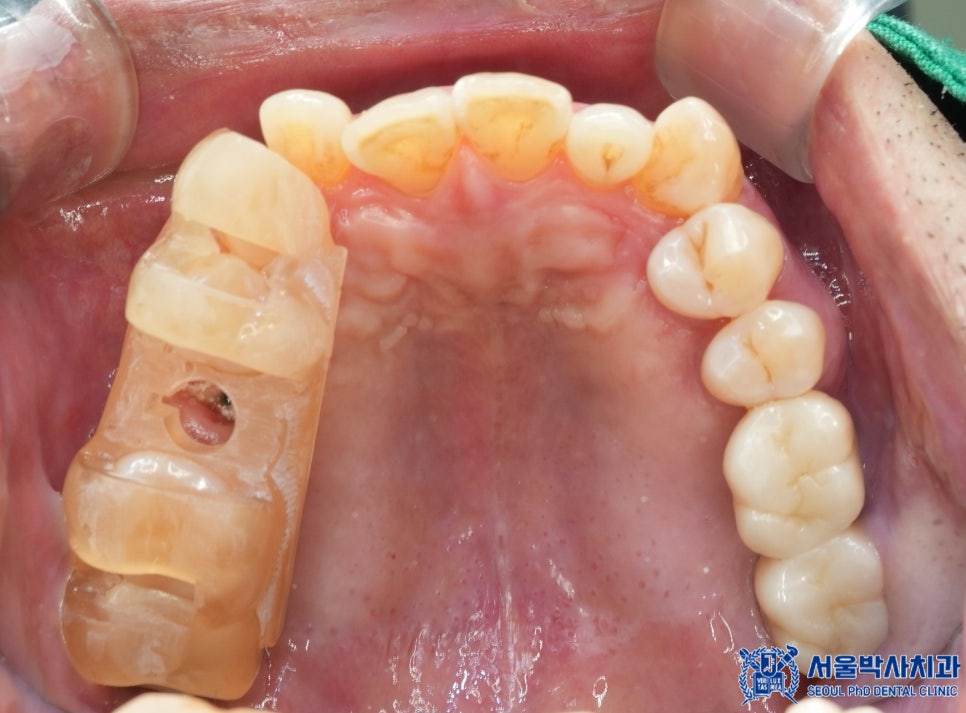

치아를 발치한 후에는

무절개 방식의 임플란트 식립을

진행하기로 하였습니다.

무절개 임플란트는

말 그대로 잇몸을 절개하지 않고

임플란트를 식립하는 방식으로,

컴퓨터 분석을 통해 미리 계산된

정확한 위치와 각도로 위 사진과 같은

수술 가이드를 제작하고,

가이드를 이용해 임플란트를 심기 때문에

수술 부위의 오차를 줄일 수 있습니다.

가이드는 컴퓨터 분석의 정밀한 계산을 통해

고성능 3D프린터로 제작됩니다.